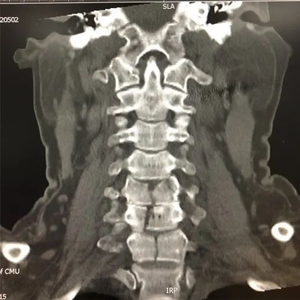

患者术前骨折影像